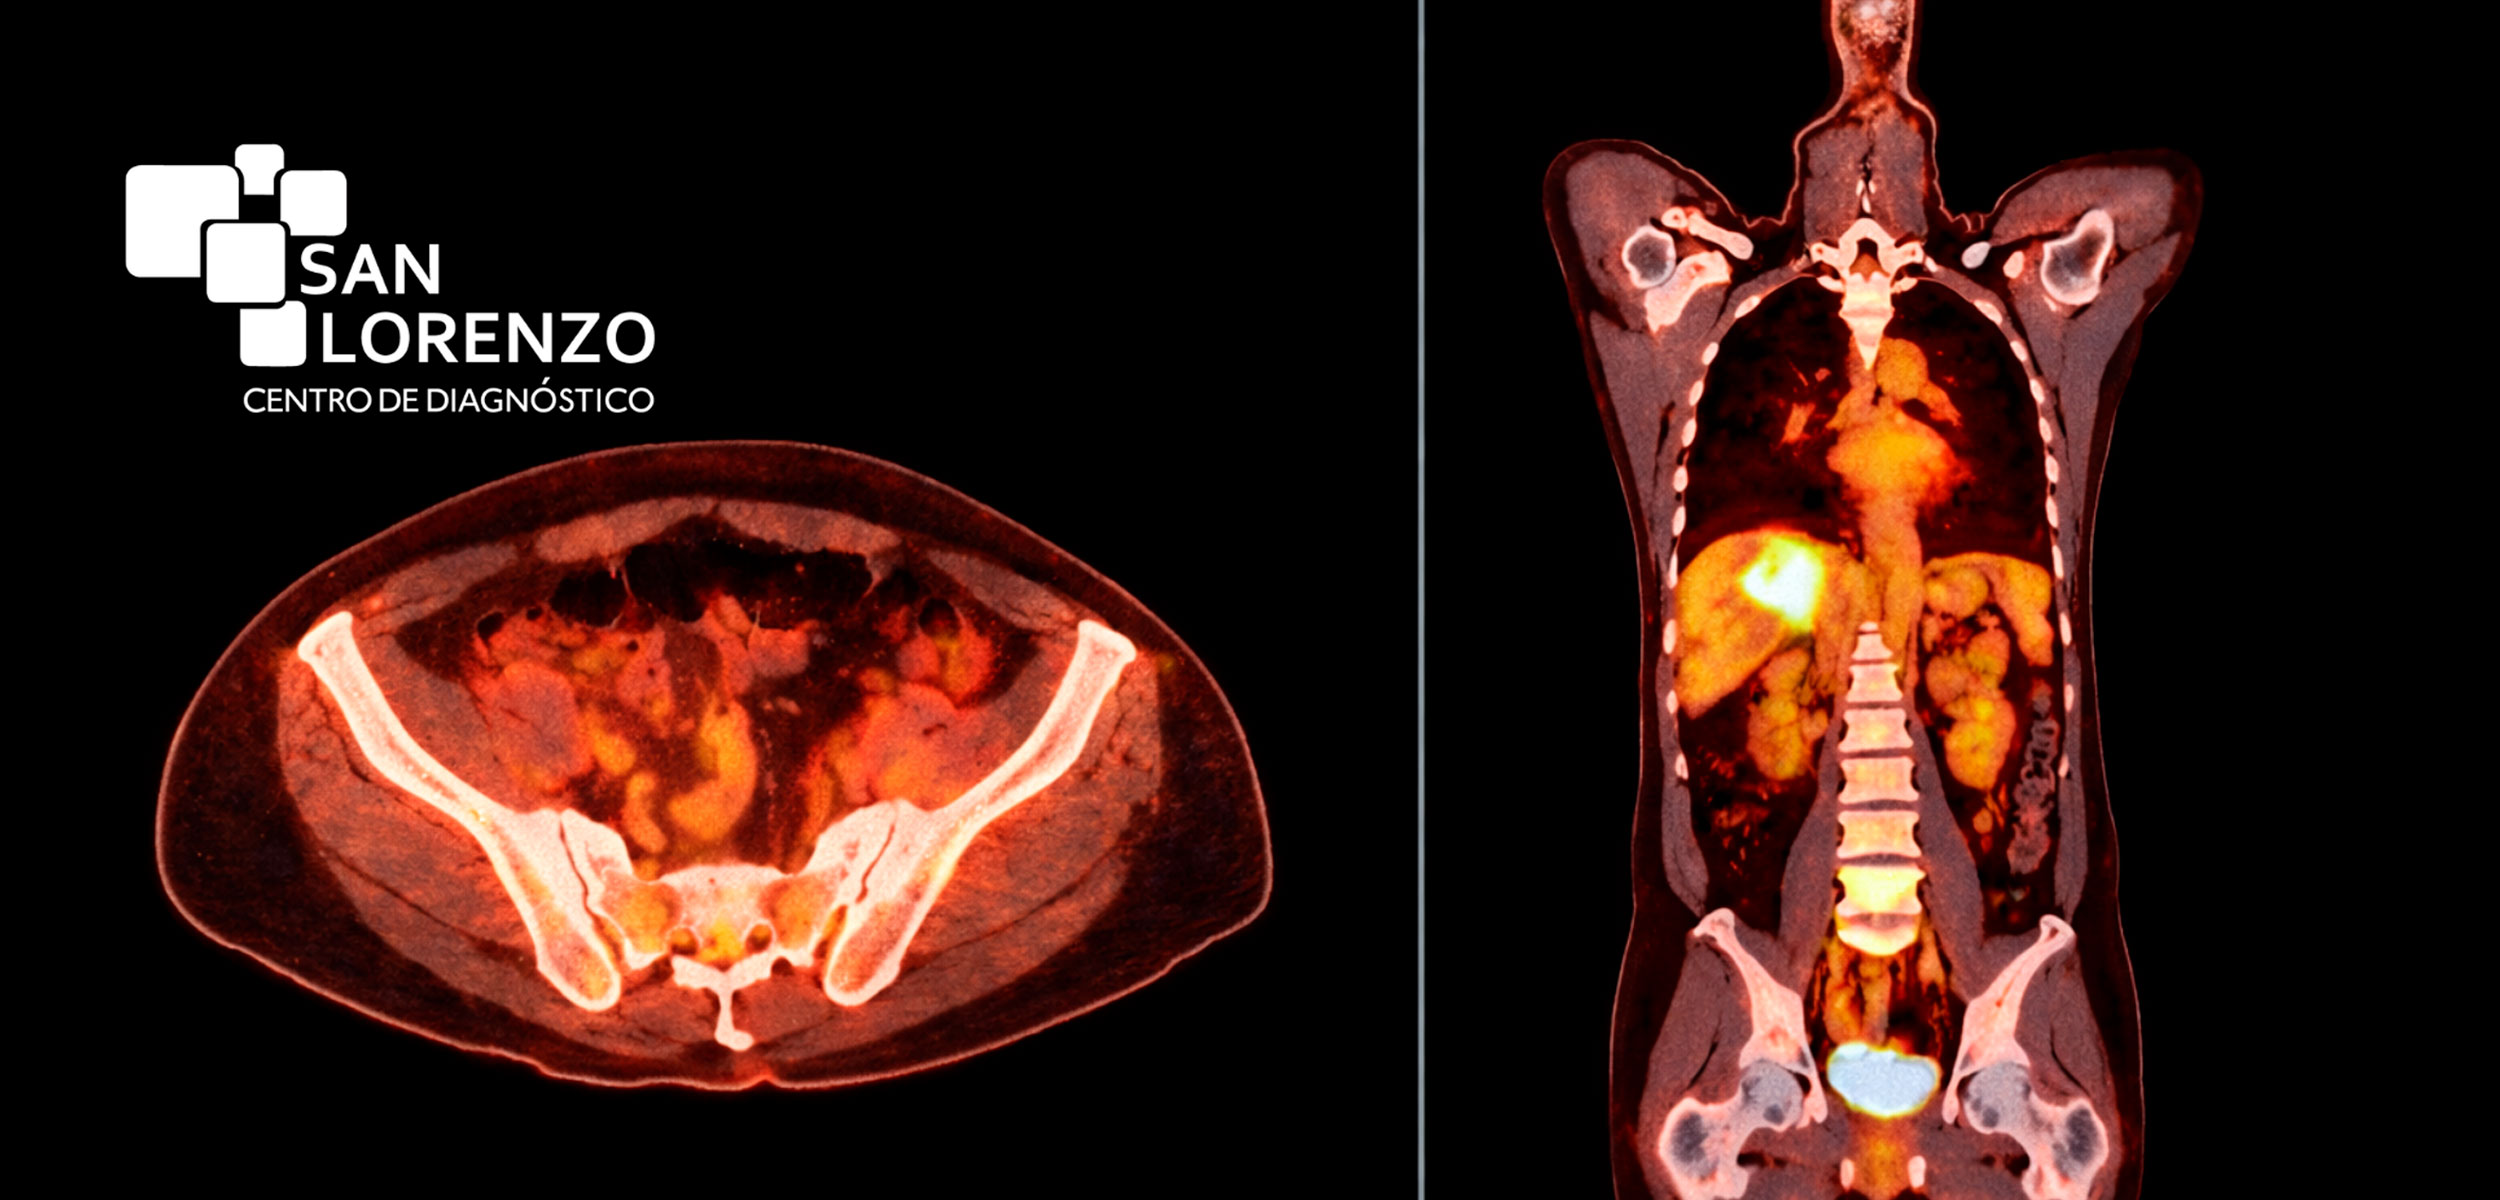

- PET/CT oncológico:: Para estudios oncológicos, tecnología híbrida que combina PET con CT o TAC, ampliamente utilizada por médicos especialistas para estudiar metástasis, controlar tumores, evaluar viabilidad cardíaca y detectar enfermedades neurológicas.